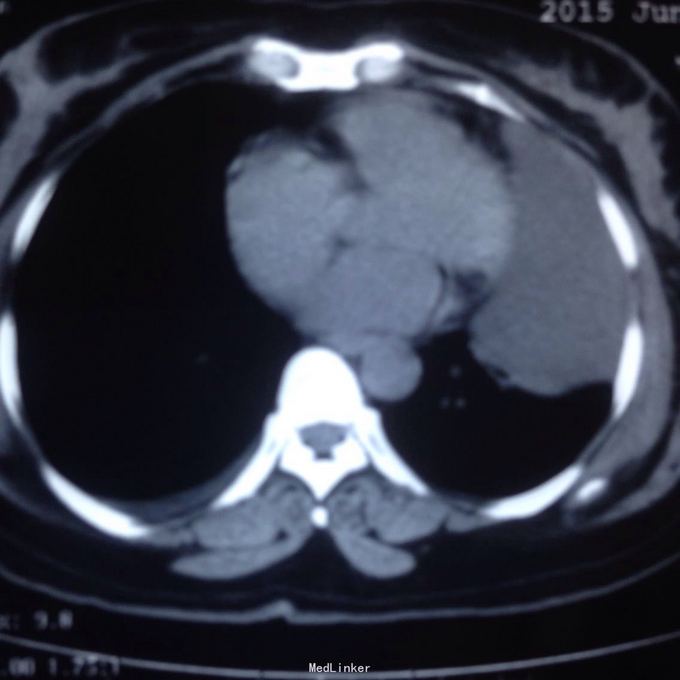

主诉:发现胸腔积液4月余。 现病史:患者4个月前因腰椎间盘突出在当地医院就诊,检查发现双侧少量胸腔积液,量不多,2个月后胸闷气短再次在当地医院复查胸部ct,提示双侧胸腔积液较前增多,左侧明显。

左侧胸腔包裹性积液? 完善胸腔b超提示左侧胸腔包裹性积液,最深处约59mm,内透声较差。予以定位后诊断性穿刺未抽出明显液体,当时考虑液体可能较粘稠或包裹分隔,遂决定予以小切口开胸探查。开胸后见胸腔积液,量约300ml,颜色较清亮,予以抽吸后在探查,见脏层及壁层胸膜无增厚及明显粘连,遂考虑不排除囊肿可能性,继续探查见胸膜顶靠近左纵隔处一囊壁,已破裂,囊壁挛缩成团,予以切除,术后病检为胸腺囊肿。

术后病检为胸腺囊肿。术后讨论:患者多次胸部ct均提示为包裹性积液,因囊肿较大,囊壁较薄,且靠近胸壁,易误诊为包裹性积液,但患者一直无发热病史,且复查ct积液位置靠胸前壁,术前应该考虑到囊肿可能,因患者经济较困难,至本院后未行增强ct,穿刺后考虑穿刺针将囊壁穿破,故开胸后未见完整囊肿,此类看似简单的病例容易由其他医院诊断误导,并且容易误诊。